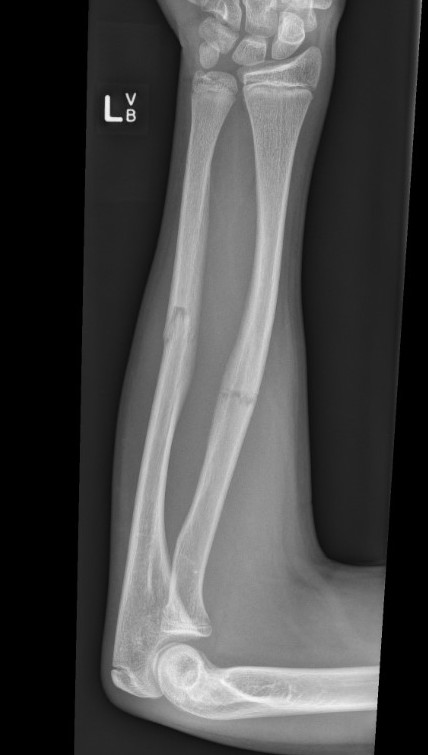

3. Intramedullary elastic nail

Advantage

- smaller scars with insertion

- easier to remove than plates

Disadvantage

- generally immobilized

- must be removed

- non anatomical reduction compared with plates with theoretical risk of loss supination / pronation

- risk of extensor tendon rupture due to prominence of nails at insertion sites

TENS technique

Technique

Radius (typically first as more difficult to reduce)

Entry point with awl 2 cm proximal to distal physis

1. Radial styloid / distal lateral entry

- ensure radial nerve / cephalic vein, 1st extensor compartment protected

2. Listers tubercle / dorsal entry

Elastic Nail size

60 - 70% of the intramedullary canal

Typically 1.5 - 2.5 mm

Fracture reduction

Avoid passing nails incorrectly multiple times as may cause compartment syndrome

Bend tip of elastic nail

May need small open reduction

Cut nail

Withdraw 1 cm, cut with endcutter, then advance

Ulna (usually reduced after radius fixation)

Entry point 2 cm distal to apophyseal plate

1. Proximal lateral

- avoids ulna nerve

3. Distal medial

Postoperative

Cast in supination to tighten interosseous membrane

Cast 6 weeks

Removal of TENS at 4 - 6 months once osseous union established